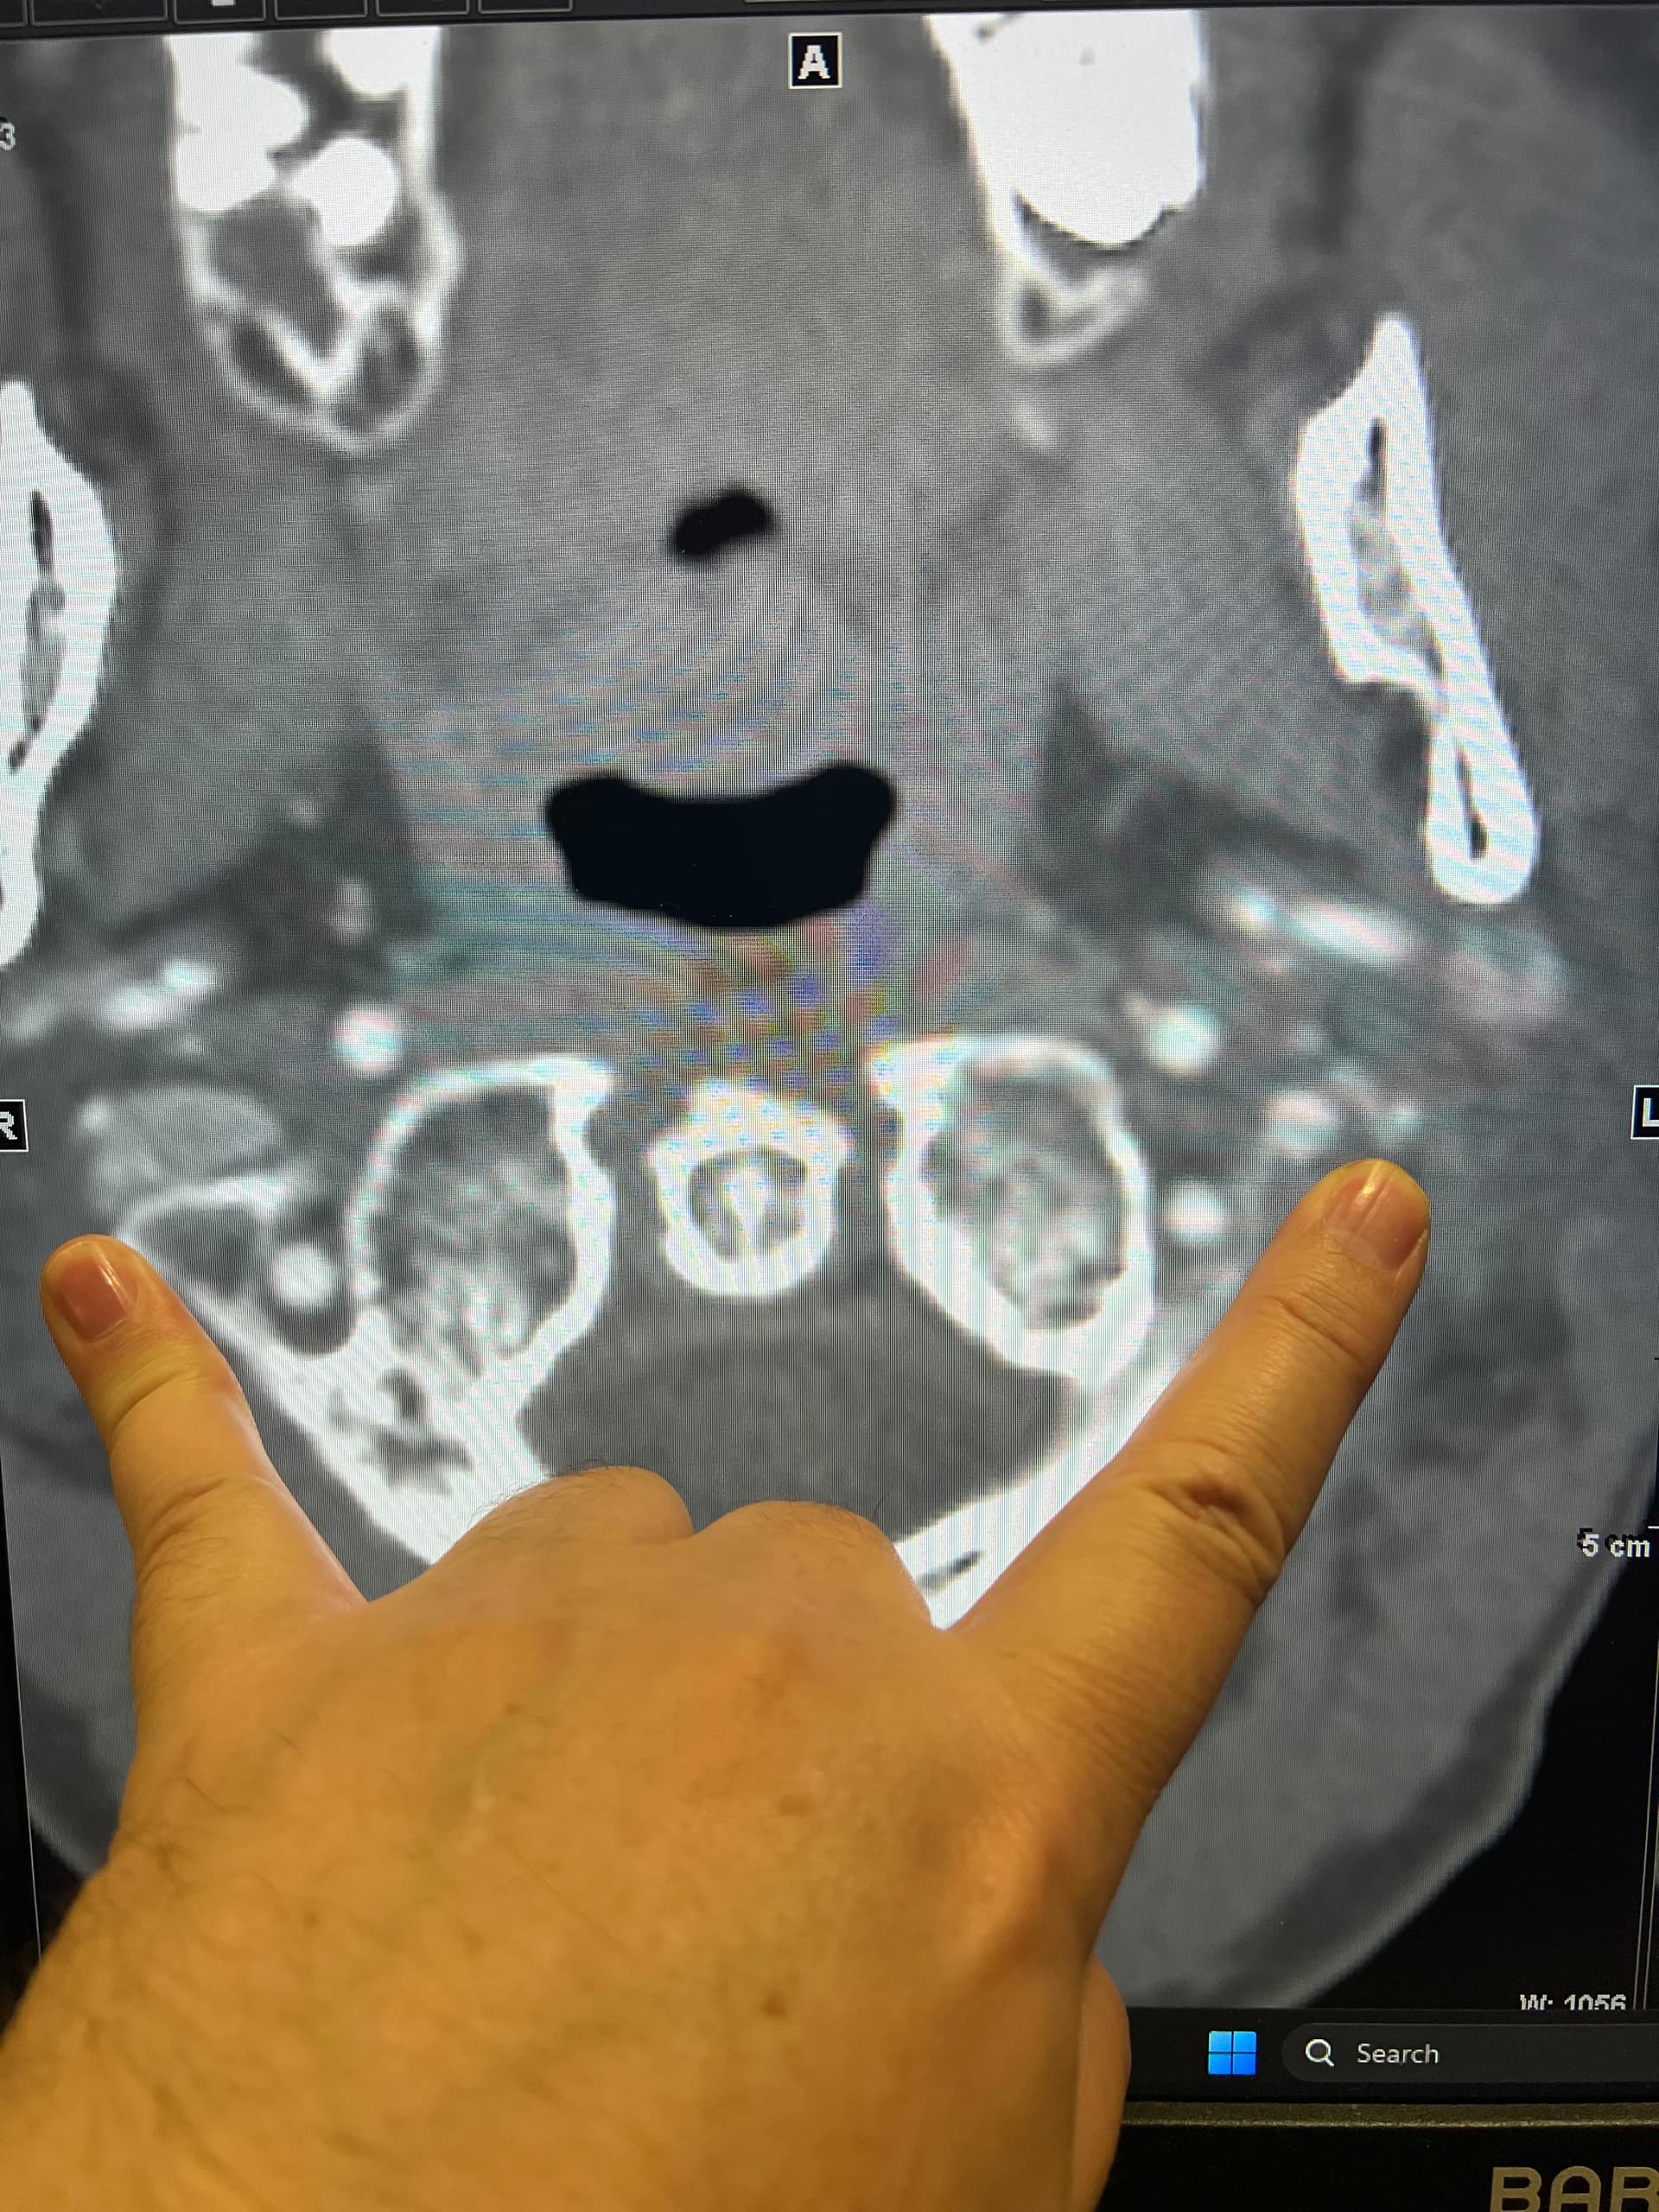

I’ve uploaded some photos. Some are repetitive but I know some in this group are skilled in reading these.

I also added some 3D photos. My left JV looks extremely narrow at around C3. Does anyone else see that?

@Luckee7 - I’ve marked some vascular structures that are above & beneath your C1 vertebra that I haven’t seen before in other imaging so am not sure what they are or if they could be involved in causing symptoms. Those above C1 appear to be “sitting” on it which appears to be causing some minor compression of those sections. They could be collateral veins, & if so, then they’re likely contributing to skull base/occipital pain.